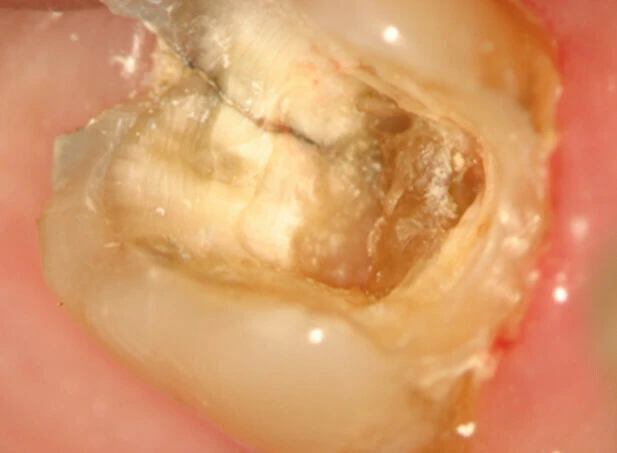

Đôi khi cần phải tháo miếng trám trên răng để có thể quan sát vết nứt rõ hơn. Nhuộm bằng Xanh Methylene bằng cách bôi thuốc lên bề mặt răng bằng đầu tăm bông, thuốc nhuộm sẽ quyên qua vùng nứt và xác định vị trí đường nứt. Chiếu sáng cũng có thể hữu ích hơn bằng cách chiếu trực tiếp ánh sáng có cường độ cao vào bề mặt răng tại đường nối men – xi măng để xem mức độ lan rộng của vết nứt. Phần răng gần với nguồn sáng sẽ hấp thu ánh sáng và phát sáng, trong khi phần răng phía bên kia của vết nứt không được sánh sáng truyền qua sẽ có màu xám hơn. Mặc dù có thể phát hiện được vết nứt bằng thuốc nhuộm hoặc ánh sáng nhưng độ sâu của vết nứt không thể lúc nào cũng xác định được.

– Tiên lượng trung bình: Nếu răng nhạy cảm khi thăm dò đường nứt mặt nhai, mảnh răng không di động, việc tiên lượng trở nên khó khăn hơn. Bệnh nhân cần hiểu được rằng điều trị nội nha có thể không giải quyết được các triệu chứng và tiên lượng cuộc điều trị chỉ ở mức khá thôi. Nếu thực hiện điều trị nội nha, cần kiểm tra các thành bên trong xoang tuỷ cẩn thận, tốt nhất là nên dùng kính hiển vi nội nha (DOM) có chiếu sáng để xác định xem đường nứt có lan rộng vào vùng buồng tuỷ và ống tuỷ không. Nếu quan sát thấy điều này, cần thông báo với bệnh nhân một lần nữa về tiên lượng của cuộc điều trị. Răng cần được trám kín và tránh dùng chốt trong trường hợp này, sau đó làm một phục hồi toàn phần gia cố tại vị trí các múi răng.